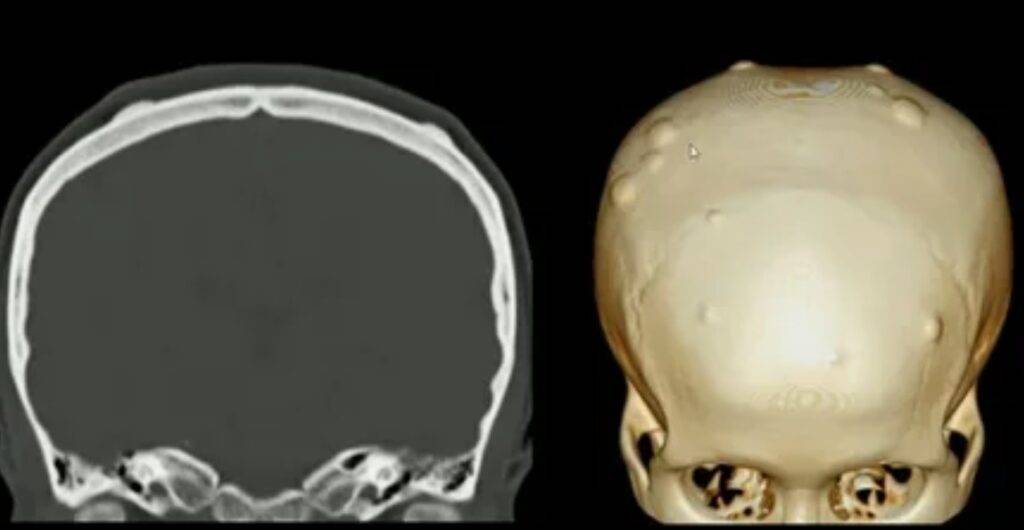

– Tomografia Computadorizada (TC): O exame “padrão ouro” para osteomas. Oferece imagens detalhadas que mostram claramente os limites e a estrutura interna do tumor. É como uma fotografia em alta definição que revela todos os detalhes.